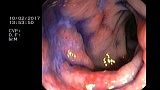

2 мл ( это мин сум, а мы делаем до 10 мл 3% перекись+200 мл физ раствора